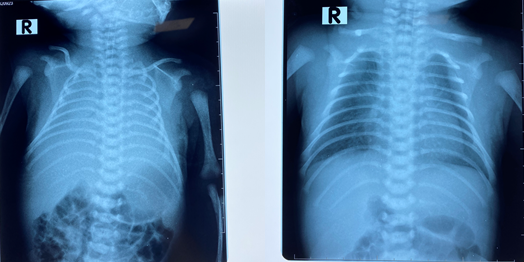

máu....và làm các xét nghiệm như chụp X quang ngực, xét nghiệm máu, đo khí

máu,... Với kinh nghiệm, trình độ chuyên môn sâu của các y bác sĩ BVTE Hải

phòng bệnh nhi được chẩn đoán: Suy hô hấp độ III / Xuất huyết phổi / Rối loạn

đông máu/ Mổ đẻ. Trẻ có nguy cơ tử vong rất cao do tình trạng chảy máu ồ ạt

X quang phổi trước và sau khi con được điều trị